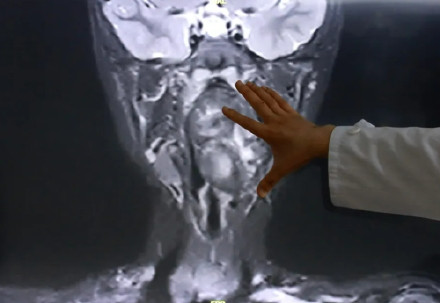

来自安徽的6岁男童小亮,因夜间打鼾就诊查出咽旁长有巨大肿瘤,因肿瘤体积巨大、紧邻颈部重要血管、严重压迫气道,手术难度与风险极高,小亮一家遂转往上海求治。复旦大学附属儿科医院耳鼻咽喉头颈外科副主任陈超表示“我们可以看出它有脂肪,有软骨,这是一对双胞胎,一个是我们正常的人发育成的人,另外一个他可能残留在这个咽旁间隙里面,就发育成了这样的一个畸胎瘤。”(新民晚报)